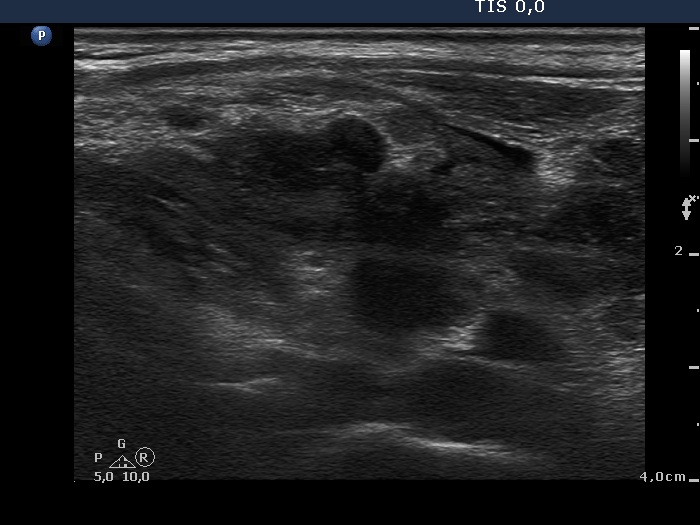

The mass in the left side of the neck corresponded to a conglomerate of multiple lymph nodes. These were irregular in shape and presented cystic and necrotic areas. There was no hilum present. The lymph nodes were avascular.